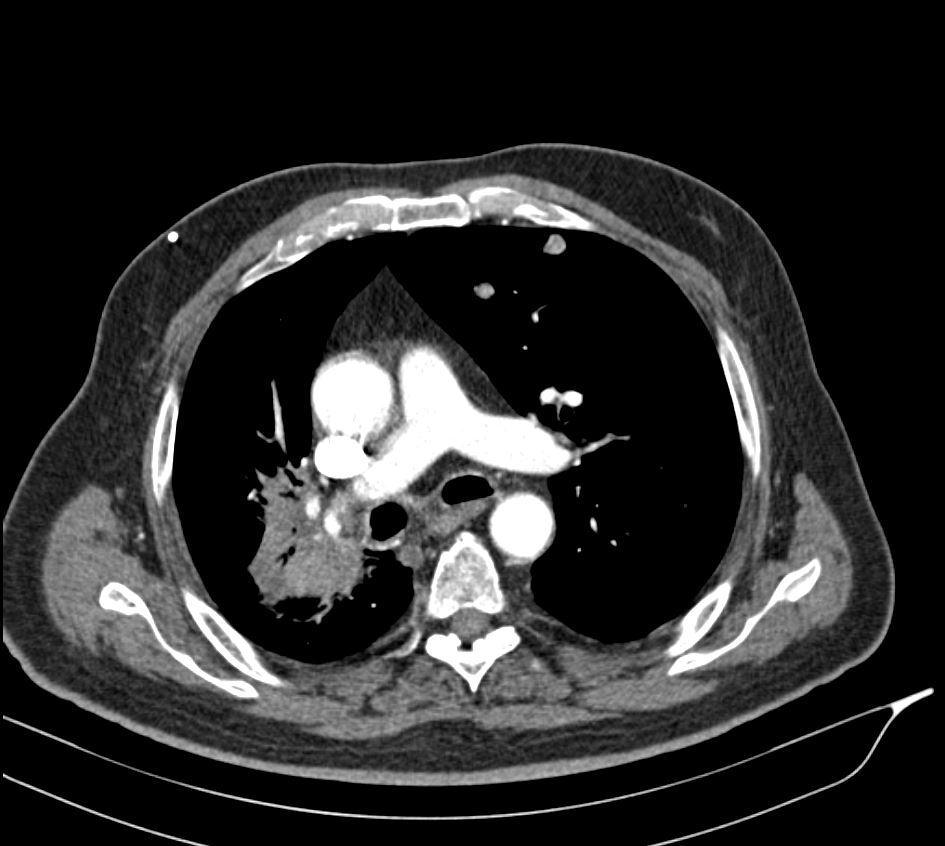

Case of the Week 25 2017 *57-year-old male. What is the most likely diagnosis? Answer Answer: Non-mucinous bronchoalveolar carcinoma and bilateral metastatic pulmonary nodules Kategori:Cases Önceki yazı Case of the Week 24 2017 Sonraki yazı Case of the Week 28 2017